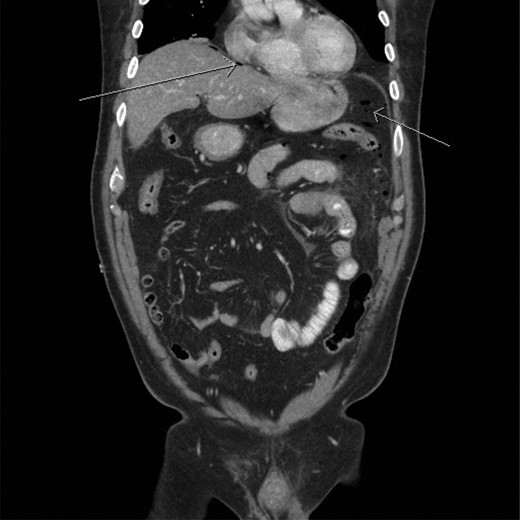

A CT scan demonstrated significant soft tissue stranding/edema of the omentum in the left hemi-abdomen. In addition, there was mild ascites and multiple scattered locules of air (Figs 3–5). No other abnormality of the small or large bowel was identified. He was admitted for observation and broad-spectrum antibiotic therapy was initiated. On post admission day 2, he became diffusely peritonitic, febrile with a temperature of 39.1°C and his oxygen requirements increased to 12 l/min.

CT scan (frontal view) demonstrating multiple locules of air (arrows).

CT scan (frontal view) demonstrating stranding/edema to the omentum (arrow).

Our case demonstrates the diagnostic dilemma that accompanies delayed bowel injuries. Laboratory tests often give nonspecific results that seldom point to a diagnosis [1]. Imaging studies also fail to establish the etiology. Our CT scan failed to demonstrate significant intraperitoneal free air (Figs 3–5). In addition, oral contrast was utilized, but gross extravasation was not identified.